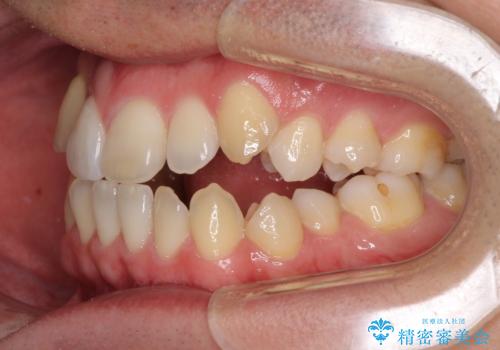

左右の八重歯が気になる ワイヤー装置での咬み合わせ改善

- 八重歯と前歯のデコボコを気にして来院された患者様です。

営業職であり、商談などで飲食をする機会が多いとのことで、インビザラインではなく、ワイヤー装置にて矯正治療を行うこととしました。